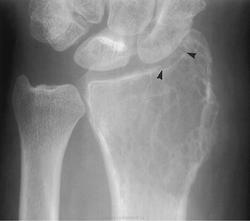

Злокачественная гигантоклеточная  опухоль возникает из доброкачественной (частота 10-20%). После операции возможно появление рецидива опухоли.

Гигантоклеточная опухоль